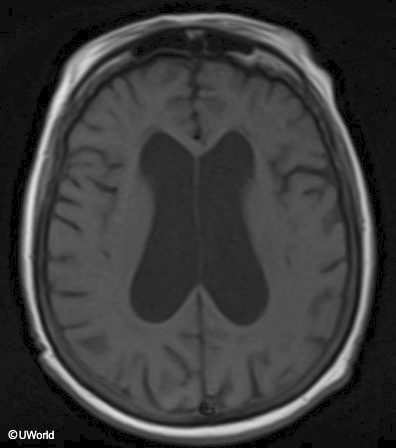

difficulty taking steps, unsteady

normal pressure hydrocephalus

tx: ventriculoperitoneal shunt